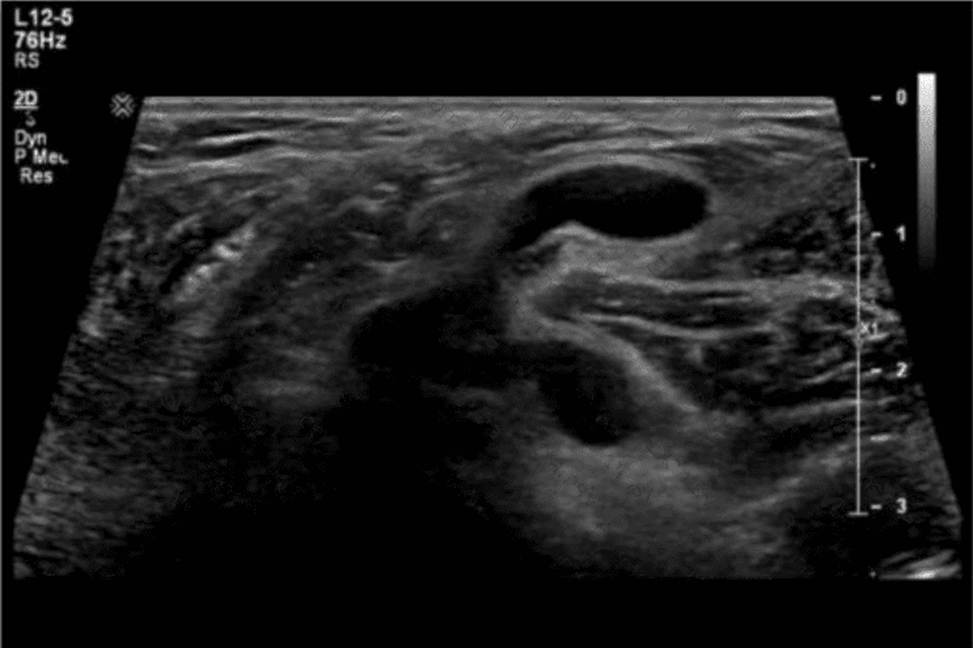

Question No : 15

Based on this image, what is the most likely clinical indication for the examination?

The ultrasound image demonstrates findings consistent with hypertrophic pyloric stenosis (HPS). This condition typically affects infants between 2 and 8 weeks of age and presents clinically with non-bilious projectile vomiting, weight loss, and dehydration.

In the ultrasound image, the classic “target” or “donut” sign can be seen in the transverse view of the hypertrophied pyloric muscle.

Key sonographic criteria for HPS include:

Pyloric muscle thickness #3 mm

Pyloric channel length #15C18 mm

This imaging appearance strongly correlates with the clinical presentation of projectile vomiting (Choice D), which is the hallmark symptom of HPS.

Comparison of answer choices:

A. Abnormal prenatal ultrasound (Choice A) is not typically associated with HPS, which develops postnatally.

B. Neonatal hyperbilirubinemia (Choice B) is not an indication for a pyloric ultrasound and affects liver /biliary imaging.

C. Red currant jelly stools (Choice C) are indicative of intussusception, not HPS.

D. Projectile vomiting (Choice D) is the most common clinical indication leading to an ultrasound exam that reveals HPS.